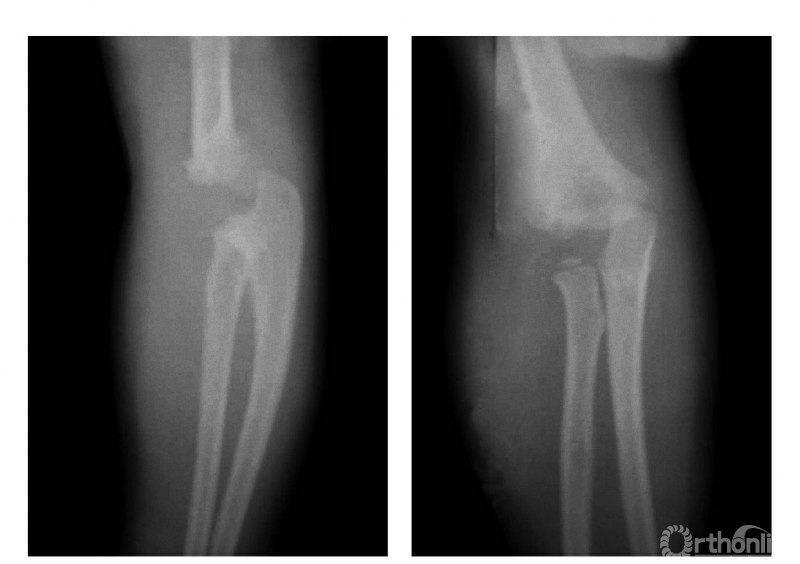

三、伸展型

例:肱骨下端骨骺分离伴前臂向后侧移位(图3)。

图3